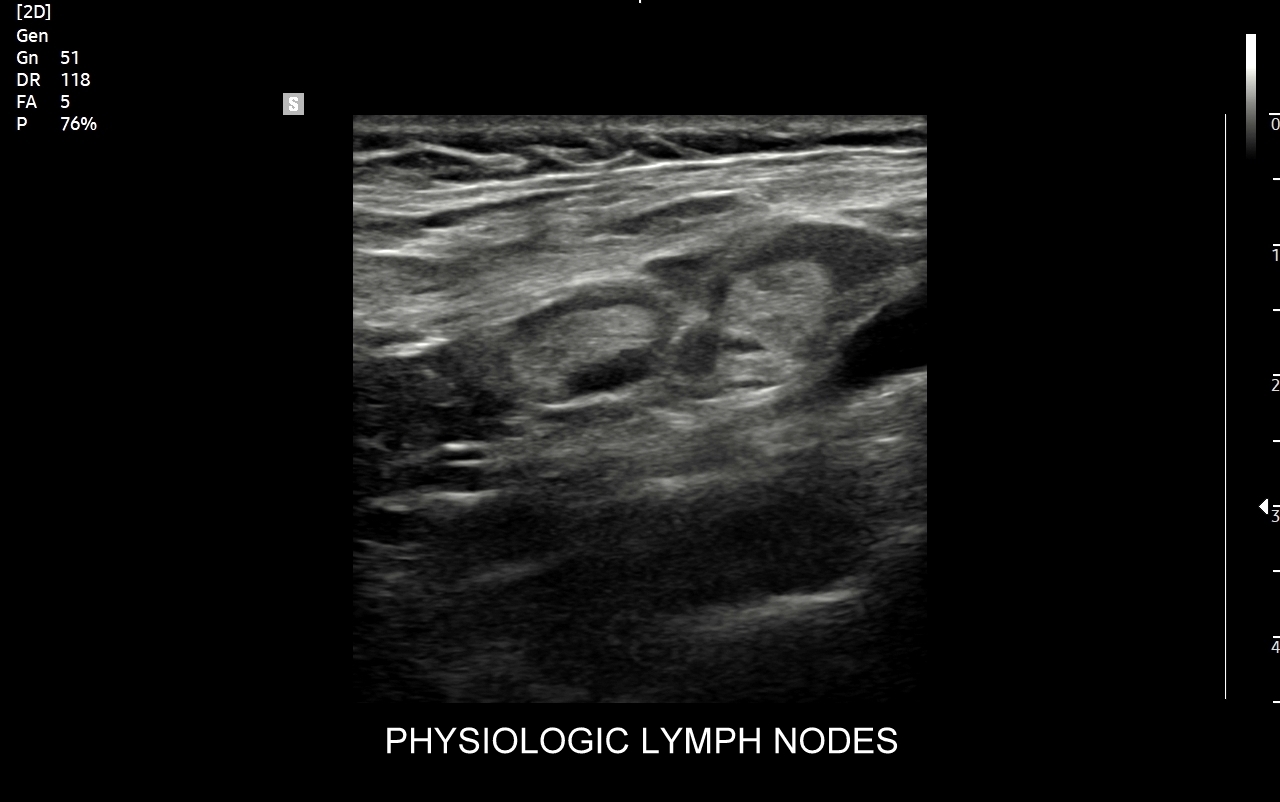

Węzły chłonne, zwane także węzłami limfatycznymi, to drobne organy, zwykle o wielkości drobnego ziarna fasoli, będące częścią układu immunologicznego, czyli odpornościowego. Występują rozproszone praktycznie w całym ciele człowieka, a połączone są między sobą naczyniami limfatycznymi. Ich główną funkcją jest filtracja limfy i krwi, a także modulowanie układu odpornościowego pod wpływem drobnoustrojów i innych antygenów w postaci stymulacji leukocytów oraz produkcji przeciwciał.

Badanie USG jest podstawową metodą obrazowania węzłów chłonnych. W jego trakcie ocenia się nie tylko wielkość węzłów, lecz także ich kształt, proporcje wymiarów, morfologię, czyli wygląd zewnętrzny oraz strukturę wewnętrzną, ich unaczynienie, spoistość, a także tkanki otoczające. W trakcie interpretacji badania pod uwagę bierze się również zbierany od pacjenta wywiad chorobowy oraz wyniki innych badań obrazowych i laboratoryjnych takich jak morfologia, OB, CRP, żelazo, ferrytyna, TIBC, innych parametrów infekcyjnych, a także onkologicznych. Ultrasonografia węzłów chłonnych jest procedurą bezpieczną i dokładną. W Pracowni dr Szczepańskiego węzły chłonne oceniane są nowoczesną metodą MPUS (multiparametryczne badanie USG), w szczególności z zastosowaniem trybów mikrounaczynienia i elastografii.